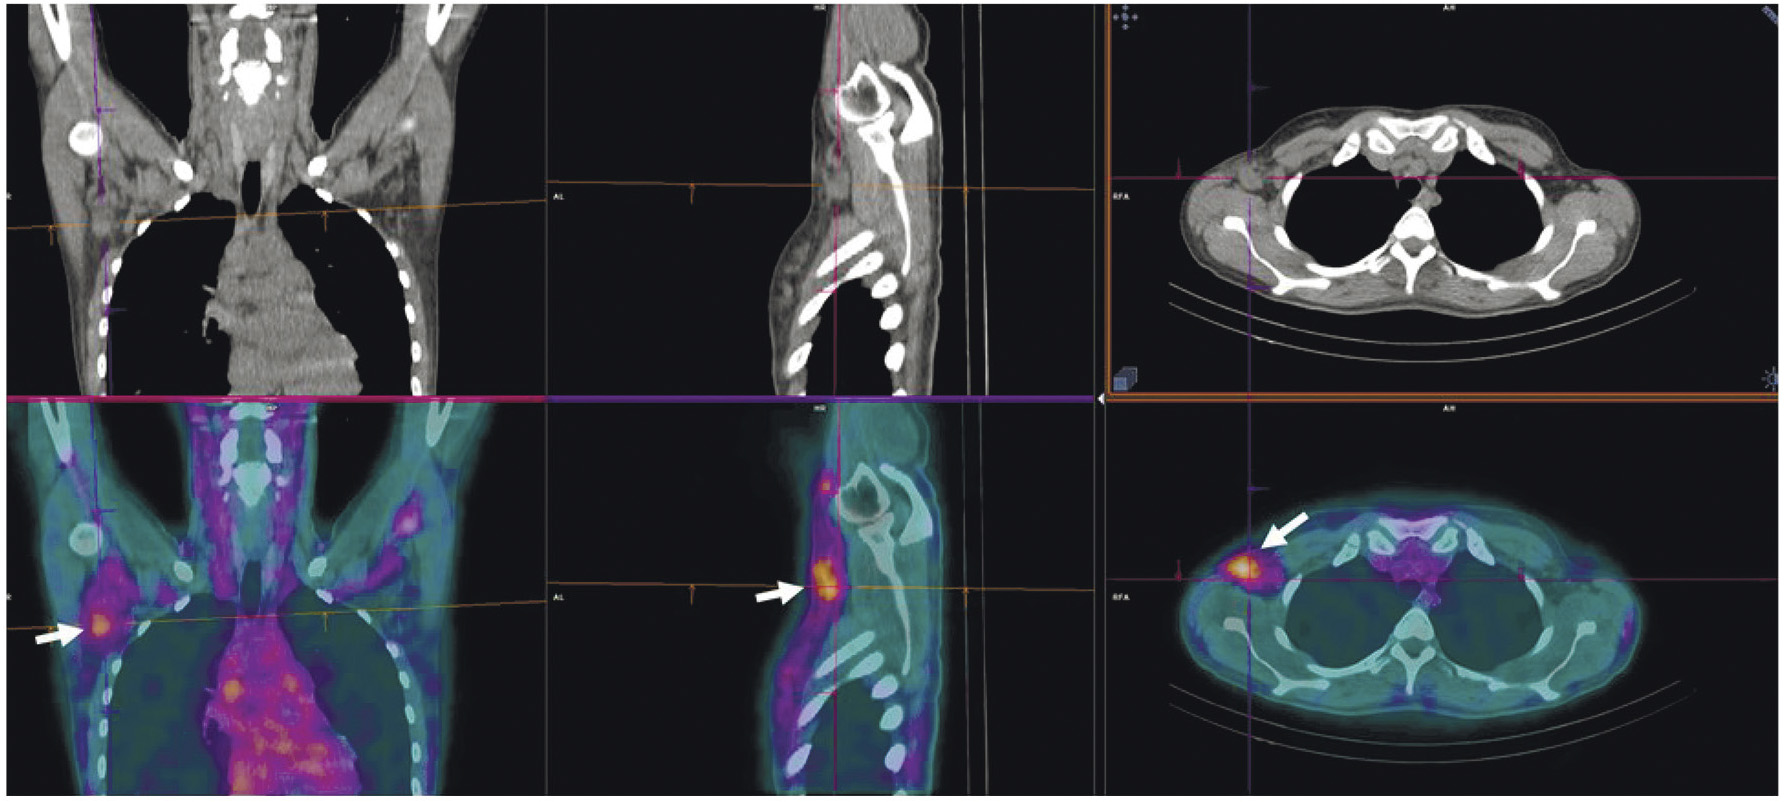

В рутинной клинической практике для ПЭТ/КТ-визуализации опухоли предстательной железы и её метастазов применяются радиофармпрепараты на основе простатспецифических мембранных антигенов, меченных 68Ga ([68Ga]Ga-ПСМА-11, [68Ga]Ga-ПСМА-617, [68Ga]Ga-ПСМА-I&T) либо 18F ([18F]F-DCFPyL, [18F]F-ПСМА-1007) [22, 23]. Главные преимущества меченных 99mТс препаратов, тропных к ПСМА, — невысокая стоимость и доступность технеция-99m, а также возможность визуализации опухоли с помощью гамма-камеры. В настоящее время для этих целей предложен ряд радиофармпрепаратов [24]. В России зарегистрированы наборы для приготовления 99mTc-HYNIC-ПСМА (“ПСМА HYNIC, 99mТс”, Польша; “Проскан, 99mТс”, Россия). Отечественный РФЛП разрабатывался в ТПУ и НИИ онкологии Томского НИМЦ. Клинические испытания 99mТс-ПСМА показали его высокую эффективность при диагностике и стадировании рака простаты, а также при отборе на радиолигандную терапию и оценке её воздействия (рис. 4).

Рис. 4. ОФЭКТ с 99mТс-ПСМА пациента с раком простаты до (а) и после (б) четырёх курсов радиолигандной терапии 177Lu-ПСМА

К настоящему времени создан ряд специфичных для GRPR радиоактивных индикаторов, которые подразделяются на агонистов и антагонистов гастрин-высвобождающих рецепторов. Считается, что антагонисты весьма перспективны в качестве основы для разработки радиофармацевтических лекарственных препаратов. Их преимущество заключается в отсутствии побочных эффектов, характерных для агонистов и обусловленных запуском клеточных сигнальных путей. Более того, плотность сайтов связывания антагонистов выше, чем у агонистов, что приводит к лучшему соотношению накопления препарата в опухоли и нормальной ткани. На базе антагониста GRPR разработан 99mТс-RM26 для ОФЭКТ/КТ-диагностики рака простаты и молочной железы. Клинические испытания этого препарата, выполненные в НИИ онкологии Томского НИМЦ, подтвердили возможность его применения для визуализации этих типов рака (рис. 5) [31, 32].

Рис. 5. ОФЭКТ/КТ с 99mТс-RM26 пациентов с раком простаты (а) и раком молочной железы (б) Стрелками обозначено накопление РФЛП в опухоли и лимфогенном метастазе